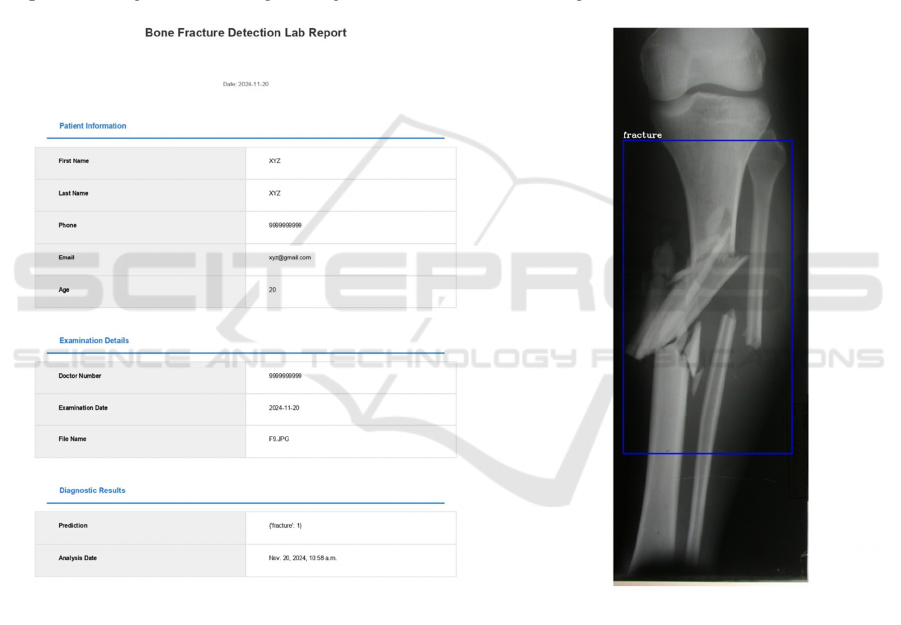

Figure 5: Generated report.